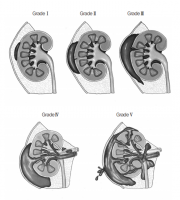

| 2019년 5월 28일 (화) 01:34 | 비뇨기계장애감정지침서 그림3.png (파일) |  |

177 KB | Sjlee | 1 | |